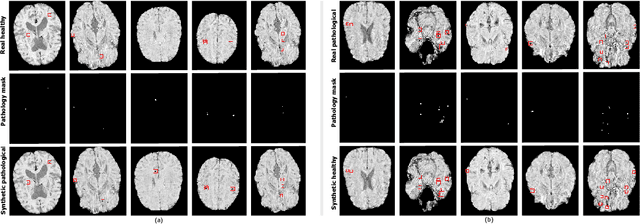

Abstract:We propose a novel framework for controllable pathological image synthesis for data augmentation. Inspired by CycleGAN, we perform cycle-consistent image-to-image translation between two domains: healthy and pathological. Guided by a semantic mask, an adversarially trained generator synthesizes pathology on a healthy image in the specified location. We demonstrate our approach on an institutional dataset of cerebral microbleeds in traumatic brain injury patients. We utilize synthetic images generated with our method for data augmentation in cerebral microbleeds detection. Enriching the training dataset with synthetic images exhibits the potential to increase detection performance for cerebral microbleeds in traumatic brain injury patients.